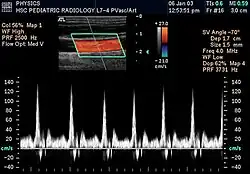

A informação Doppler é representada graficamente com um Doppler espectral, ou como uma imagem utilizando Doppler direcional ou Doppler de potência (Doppler não direcional). A frequência Doppler enquadra-se na gama audível e é representada por altifalantes estéreo, produzindo um som pulsante distinto, embora sintético.

O Doppler colorido é essencialmente o sistema informático integrado no aparelho de ultrassons. Atribui unidades de cor dependendo da velocidade e direção do fluxo sanguíneo. Por convenção, o vermelho é atribuído ao fluxo em direção ao transdutor e o azul ao fluxo em direção oposta.

A maioria dos aparelhos modernos utiliza ultrassons Doppler pulsados, produzindo um Doppler de fluxo colorido, para medir o fluxo no centro ou na periferia de um vaso sanguíneo.[3] Os dispositivos de onda pulsada transmitem e recebem uma série de impulsos, recebendo geralmente a informação antes de enviar o próximo. A variação da frequência de cada pulso é ignorada, mas as variações de fase relativas dos pulsos são utilizadas para obter a variação da frequência, uma vez que a frequência é a taxa de variação dessa fase. A principal vantagem do Doppler pulsado em relação à variedade de onda contínua é que a informação da distância é obtida (o tempo entre a transmissão e a recepção dos impulsos pode ser convertido em distância, conhecendo-se a velocidade do som). A desvantagem do Doppler pulsado é que as medições podem sofrer aliasing. O termo "ecografia Doppler" ou "sonografia Doppler" tem sido aceite para se referir às versões pulsada e contínua, apesar dos diferentes mecanismos pelos quais cada uma mede o fluxo.